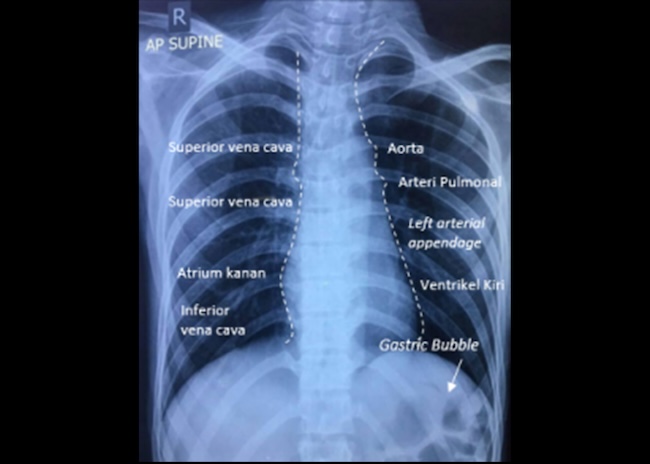

Dari gambaran rontgen toraks pun dapat memperkirakan bagian dari jantung dengan melihat siluet jantung. Batas kanan biasa dibentuk oleh atrium kanan di mana vena cava superior masuk, dan vena cava superior dan inferior dapat terlihat di batas bawah kanan jantung. Sebaliknya, batas kiri terbentuk dari ventrikel kiri dan left atrial appendage.[9]

G. Great Vessels / Gastric Bubble

Pada bagian ini, lihat ukuran aorta serta bentuk dari pembuluh darah pulmonal. Aortic knob harus terlihat jelas. Selain itu, perhatikan juga adanya gastric bubble, yaitu area kehitaman (radiolucent) yang biasanya berbentuk bulat dan terletak di bawah hemidiafragma kiri. Gastric bubble menunjukan adanya udara di fundus lambung.[10]

Gambar 1. Rontgen Toraks. Sumber: dr. Immanuella, 2018.

Sebagai contoh, interpretasi rontgen toraks pada Gambar 1 adalah:

- Ukuran jantung <50% menunjukkan tidak adanya perbesaran jantung. Tidak tampak kalsifikasi aorta

- Aorta dan arteri pulmoner pasien baik pada rontgen toraks ini, tetapi tidak tampak gastric bubble di bawah hemidiafragma kiri.

- Tidak ada pelebaran mediastinum. Trakea di tengah dan tidak tampak deviasi.